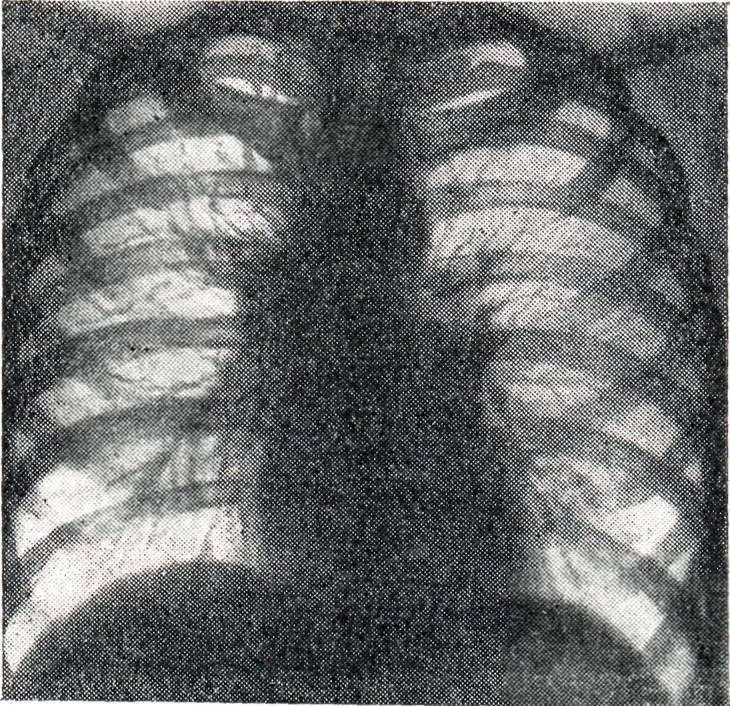

Бронхагенное рассеивание казеозного материала ведёт к развитию тяжёлых бронхопневмоний (лобулярио-казеозных). Осложнения. Течение Б. нередко осложняется плевритом (железисто-плевральный синдром); характерны междолевые экссудативные плевриты (чаще при первичном туберкулёзе). При большом увеличении группы лимф, узлов может возникнуть ателектаз сегмента или доли лёгкого. Длительное существование ателектазов может привести к фибротизации спавшегося участка с образованием бронхоэктазов. Диагноз ставится на основании комплексного клинико-рентгенологического обследования, анамнеза (контакта с туберкулёзным больным), характера туберкулёзной интоксикации. Подтверждением туберкулёзной этиологии процесса в висцеральных грудных лимф, узлах является туберкулиновая проба (см. Туберкулинокагностика). При туберкулёзном Б. чаще встречается резко положительная туберкулиновая проба. При туберкулёзном Б. с тяжёлым осложнённым течением туберкулиновые пробы могут быть слабоположительными (состояние анергии). Выявлению клинически не диагностируемых и осложнённых форм Б. способствует также бронхоскопия (см.), при к-рой нередко обнаруживаются инфильтративные изменения стенки бронха и свищи соответственно расположению патологически изменённого лимф. узла. Основной метод диагностики Б. — рентгенологический. Рентгенодиагностика имеет целью установить наличие увеличенных или уплотнённых висцеральных грудных лимф, узлов. При этом руководствуются принципом целенаправленного рентгенологического исследования области средостения путем применения различных способов послойной рентгенографии (томография лучами повышенной жесткости с продольным, поперечным и косым направлением размазывания теней, с выделением толстых слоев — зонография). Послойная рентгенография должна быть многопроекционной (см. Полипозиционное исследование). Особенно ценнов диагностике поражений труднодоступных для выявления групп лимф. узлов (бифуркационных, левых трахео-бронхиальных, парааортальных, артериального протока, бронхо-пульмональных) использование не только прямых и боковых, но и косых проекций с поворотом грудной клетки на 45° в правом и левом лопаточном положении. На послойных рентгенограммах выявляются сочетанные поражения бронхов и лимф, узлов, а в отдельных случаях — лимфо-бронхиальные свищи и компрессионные стенозы. При опухолевидной форме Б. перифокальные явления в прилегающей лёгочной ткани обычно отсутствуют. Тень корня увеличена, менее структурна, отдельные сосудистые стволы корня плохо различимы (рис. 1). Проекции бронхов менее отчётливы, тень корня почти сливается с тенью средостения. Наружная волнообразная или бугристая граница деформированного корня проецируется в виде отчётливой, хотя и не всегда резкой линии, что зависит от отсутствия или наличия воспалительных изменений в капсуле лимф, узлов. При одностороннем опухолевидном Б. изменения корня противоположного лёгкого менее выражены (рис. 2), на стороне поражения лёгочный рисунок несколько усилен, прилежащие листки междолевой плевры уплотнены (рис. 3). При вовлечении в процесс медиастинальной плевры бугристые наружные контуры корня или средостения могут исчезать. Тень средостения расширена, имеет гладкие контуры.